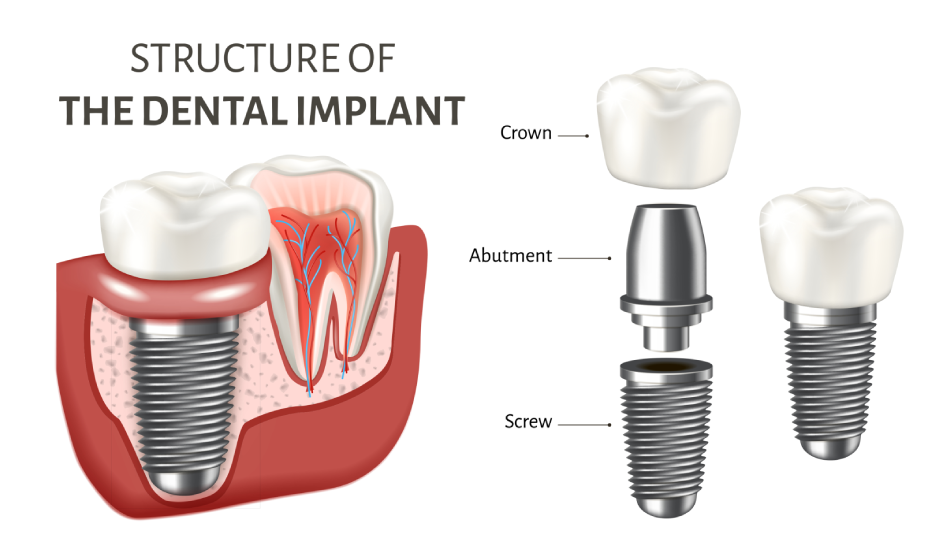

SeptemberDental Implants

The Gold Standard for Tooth Replacement: Dental Implants Losing a tooth—whether from injury, decay, or periodontal disease—affects much more than appearance. It can interfere with proper chewing, alter speech, and …